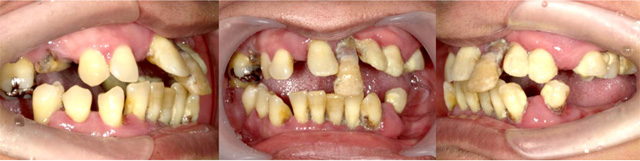

オールオン4の治療例:1

治療前

治療後

オールオン4の治療例:2